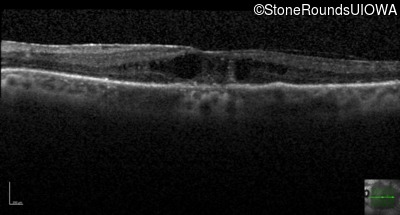

Age at visit: 66 years

OD OS

Age at visit: 69 years